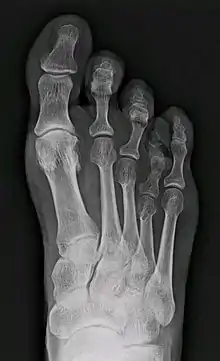

X-ray of congenital brachymetatarsia involving fourth metatarsal bone

Brachymetatarsia is a rare malformation that causes one or more toes to be abnormally short. The condition is characterized by a metatarsal arch shortness of more than 5 mm. The condition is more common in females, and the incidence reported in the literature ranges from 0.02% to 0.05%. Brachymetatarsia appears to be the result of epiphyseal plate retardation or premature closure. The etiology may be congenital and idiopathic, posttraumatic, postinfection, iatrogenic, or secondary to a systemic disease such as cancer, sickle cell disease, pseudohyperparathyroidism, Turner's syndrome, Down's syndrome, Apert syndrome, athyroidism, or osteodystrophy.[2]

It most frequently involves the fourth metatarsal. If it involves the first metatarsal, the condition is known as Morton's syndrome. Treatment is via a number of differing surgical procedures.[3]